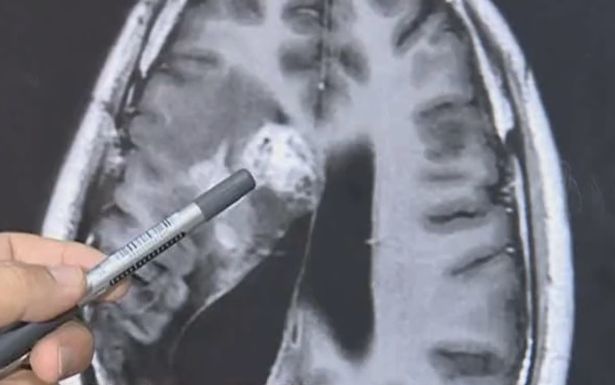

Con sán dây sống trong não bệnh nhân.

Theo Mirror, một người đàn ông bị nhiễm sán dây dài 12cm lưu trú trong não và ăn não một cách từ từ trong suốt 15 năm qua.

Wang Lei bắt đầu cảm thấy đau phía bên trái đầu từ năm 2004, và sức khỏe không ngừng giảm sút kể từ đó.

Nhiều chuyên gia và bác sĩ từng nghi Wang bị u não. Trải qua nhiều năm chữa trị, tình trạng của người đàn ông Trung Quốc tiếp tục xấu đi, thỉnh thoảng bị co giật và ngất.

Ảnh chụp CT não của Wang.

Năm 2018, các bác sĩ phát hiện một con sán sống trong não bệnh nhân. Ở thời điểm đó, các bác sĩ chỉ định biện pháp chữa trị không phẫu thuật vì ký sinh trùng nằm ở khu vực nhạy cảm, rất khó phẫu thuật.